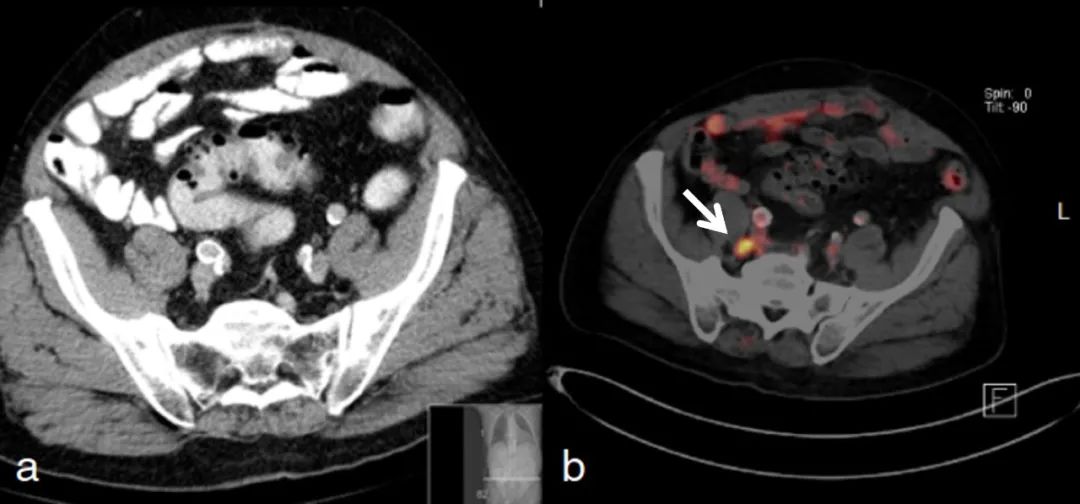

Bluemel 在68Ga-PSMA PET/CT顯像對前列腺癌患者補救性放療計劃和前列腺切除術后持續PSA值或生化復發的影響研究中發現(1),42%的病例因為68Ga-PSMA PET/CT 發現復發或淋巴結轉移,從而改變治療計劃。Garg等人的研究也表明(2-3), PET/CT在宮頸癌的初始分期和復發中表現出較高的敏感性和特異性,PET/CT的優勢是可以檢測到腹主動脈旁淋巴結和盆腔淋巴結來制定治療計劃。

68Ga-PSMA PET 發現轉移的淋巴結 (白色箭頭所示),改變腫瘤分期